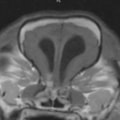

水頭症とは、頭蓋内の脳室系に異常な拡張を伴う病気です。犬や猫では、様々な疾患に起因して脳室の拡張が生じる後天的水頭症と先天性水頭症があります。先天性水頭症が好発する犬種は、チワワ、ポメラニアン、ヨーキーなどが挙げられます。

超音波検査、CT検査、MRI検査が有効です。

正常な脳室

拡張した脳室